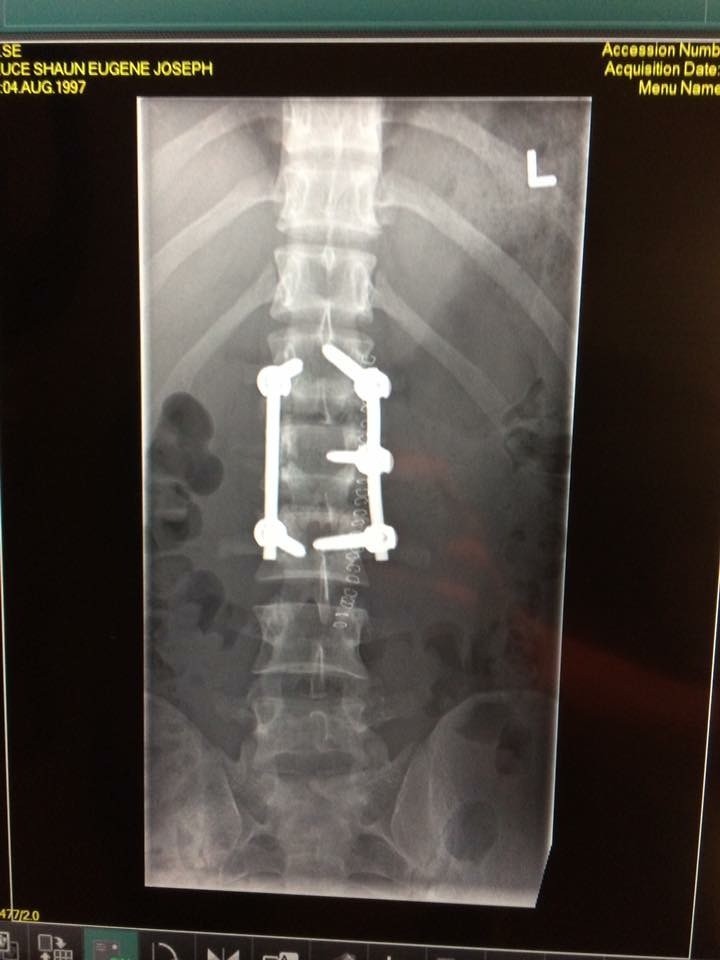

Before and after my scoliosis spinal fusion ) [OC] XRayPorn Stationary Bike After Spinal Fusion Exercising using equipment available in most gyms or for purchase for the home, such as stationary bikes, elliptical trainers, and stair climbers. Learn how to cycle safely and effectively after a spine fusion, depending on the location, type, and maturity of the fusion. Learn how to exercise safely and effectively after a spinal fusion, based on your fusion level and. Stationary Bike After Spinal Fusion.

Xrays of my spinal fusion surgery before and after pics Stationary Bike After Spinal Fusion Once you've received your doctor's blessing, ease back into cycling slowly. A detailed guide for patients who undergo cervical spinal fusion surgery, with instructions on pain management, posture, exercises, and. Learn how to exercise safely and effectively after a spinal fusion, based on your fusion level and your doctor's advice. Learn how to cycle safely and effectively after a spine. Stationary Bike After Spinal Fusion.

Spinal Fusion Before And After Stationary Bike After Spinal Fusion Exercise after spinal fusion surgery. Cycling is a fantastic workout for patient’s recovering from spine surgery because it is much lower impact than running and other exercises. Exercising using equipment available in most gyms or for purchase for the home, such as stationary bikes, elliptical trainers, and stair climbers. Learn how to exercise safely and effectively after a spinal fusion,. Stationary Bike After Spinal Fusion.